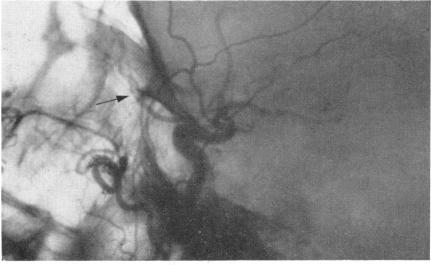

Arteriography and phlebography in the diagnosis of orbital affections.

Bull N Y Acad Med. 1968 Apr;44(4):409-30.